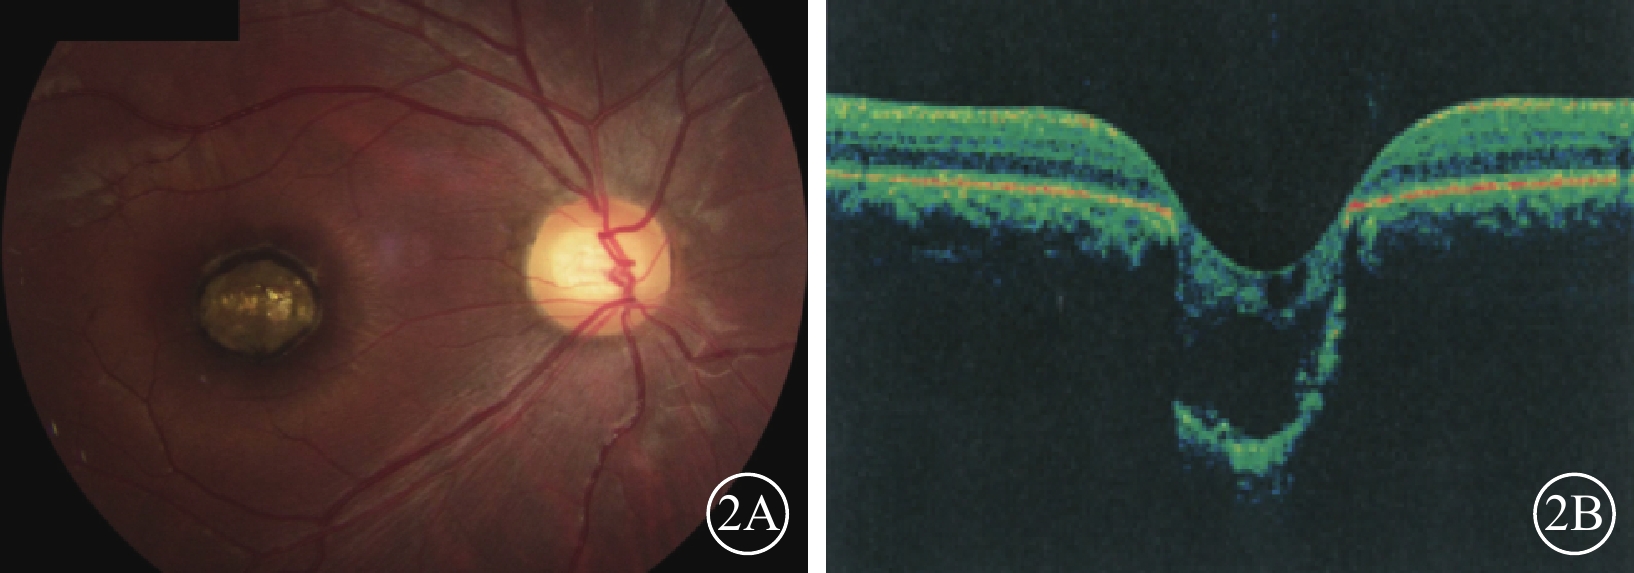

圖2

例2患者右眼彩色眼底、OCT像。2A. 彩色眼底像,黃斑區可見一大小約1.0 DD的邊界清晰的橢圓形缺損;2B. OCT像,病灶區視網膜脈絡膜組織隨鞏膜組織向外凹陷,凹陷區域內視網膜神經上皮層薄變及缺損,神經上皮層間呈囊樣變化伴淺脫離

圖2

例2患者右眼彩色眼底、OCT像。2A. 彩色眼底像,黃斑區可見一大小約1.0 DD的邊界清晰的橢圓形缺損;2B. OCT像,病灶區視網膜脈絡膜組織隨鞏膜組織向外凹陷,凹陷區域內視網膜神經上皮層薄變及缺損,神經上皮層間呈囊樣變化伴淺脫離

例2 例1之兄,29歲。因自幼雙眼視力差與例1同時來我院就診。眼科檢查,雙眼眼位正位,無眼球震顫。右眼視力0.1,?7.50 DS/+4.00 DC×90°=0.1;左眼視力0.05,?4.00 DS/+3.00 DC×85°=0.1。右眼眼壓19 mmHg,左眼眼壓20 mmHg。雙眼瞳孔對光反射遲鈍,其余眼前節檢查正常。雙眼視盤邊界清楚,顏色基本正常,C/D=0.3;視網膜平復,黃斑區可見約1.0 DD大小的類圓形缺損區(圖2A);其邊界清晰,凹陷深,中間可見灰白色鞏膜組織,脈絡膜毛細血管缺失。OCT檢查,雙眼黃斑缺損區視網膜脈絡膜組織隨鞏膜組織局限性向外凹陷,凹陷區域內視網膜神經上皮層變薄,部分缺損,神經上皮層間囊樣改變,其下見淺脫離(圖2B)。基因檢查:患者攜帶下列雜合突變:(1)CEP290 c. 3573+3A>G;(2)CEP290 c. 366A>G,p. K122K。診斷:雙眼先天性黃斑缺損(色素型)。

圖2

例2患者右眼彩色眼底、OCT像。2A. 彩色眼底像,黃斑區可見一大小約1.0 DD的邊界清晰的橢圓形缺損;2B. OCT像,病灶區視網膜脈絡膜組織隨鞏膜組織向外凹陷,凹陷區域內視網膜神經上皮層薄變及缺損,神經上皮層間呈囊樣變化伴淺脫離

圖2

例2患者右眼彩色眼底、OCT像。2A. 彩色眼底像,黃斑區可見一大小約1.0 DD的邊界清晰的橢圓形缺損;2B. OCT像,病灶區視網膜脈絡膜組織隨鞏膜組織向外凹陷,凹陷區域內視網膜神經上皮層薄變及缺損,神經上皮層間呈囊樣變化伴淺脫離

例2 例1之兄,29歲。因自幼雙眼視力差與例1同時來我院就診。眼科檢查,雙眼眼位正位,無眼球震顫。右眼視力0.1,?7.50 DS/+4.00 DC×90°=0.1;左眼視力0.05,?4.00 DS/+3.00 DC×85°=0.1。右眼眼壓19 mmHg,左眼眼壓20 mmHg。雙眼瞳孔對光反射遲鈍,其余眼前節檢查正常。雙眼視盤邊界清楚,顏色基本正常,C/D=0.3;視網膜平復,黃斑區可見約1.0 DD大小的類圓形缺損區(圖2A);其邊界清晰,凹陷深,中間可見灰白色鞏膜組織,脈絡膜毛細血管缺失。OCT檢查,雙眼黃斑缺損區視網膜脈絡膜組織隨鞏膜組織局限性向外凹陷,凹陷區域內視網膜神經上皮層變薄,部分缺損,神經上皮層間囊樣改變,其下見淺脫離(圖2B)。基因檢查:患者攜帶下列雜合突變:(1)CEP290 c. 3573+3A>G;(2)CEP290 c. 366A>G,p. K122K。診斷:雙眼先天性黃斑缺損(色素型)。